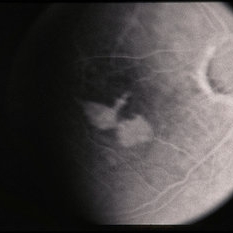

---thumb.jpg/image-square;max$300,300.ImageHandler) Age Related Macular Degeneration - Geographic Atrophy

Age Related Macular Degeneration - Geographic Atrophy

May 3 2013 by Suber S. Huang, MD, MBA, FASRS

Geographic Atrophy.

Imaging device: Retina Diseases Imaging Reading Center

Condition/keywords: advanced geographic atrophy, atrophic scar, atrophic spot, geographic atrophy, macula lesion, pigment epithelial atrophy, red-free, window defect